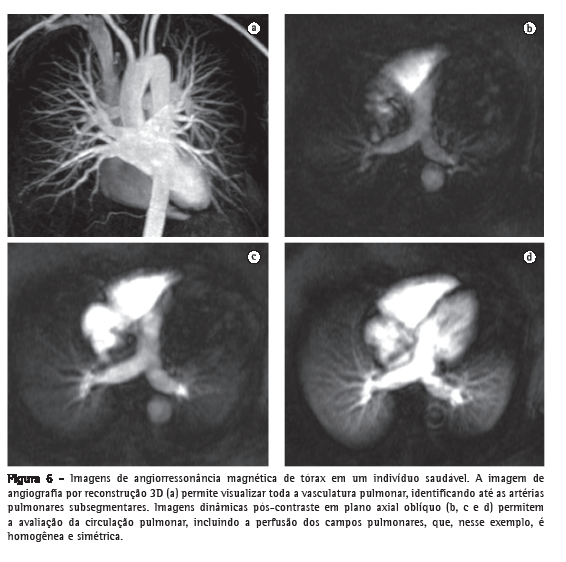

Utilizando as novas técnicas de angio-RM, principalmente as sequências GE 3D pós-Gd, atualmente já é possível identificar-se até as pequenas artérias pulmonares subsegmentares (de 4ª ordem) de um pulmão normal. Essa técnica permite a obtenção de imagens com alta resolução temporal, adquiridas a cada 1,0-1,5 segundos, que podem ser utilizadas também para o estudo de perfusão do parênquima pulmonar (Figura 6).(40) As sequências GE que mostram o fluxo sanguíneo com alto sinal, também chamadas de sangue brilhante (sequências GE balanceadas, cine-RM e contraste de fase), permitem a avaliação dos grandes vasos torácicos sem a necessidade da administração de contraste, além de possibilitarem a avaliação dinâmica e a mensuração do fluxo nas artérias pulmonares e aorta, permitindo assim estudos não somente morfológicos, mas com o acréscimo de informações funcionais.(41)